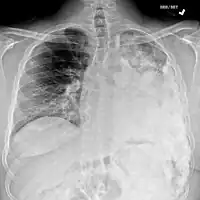

-

Osteosarcoma of the distal femur -

Metastatic osteosarcoma to the left chest -

Telangiectactic osteosarcoma of the humerus

Most times, the early signs of osteosarcoma are caught on X-rays taken during routine dental check-ups. Osteosarcoma frequently develops in the mandible (lower jaw); accordingly, dentists are trained to look for signs that may suggest osteosarcoma. Even though radiographic findings for this cancer vary greatly, one usually sees a symmetrical widening of the periodontal ligament space. If the dentist has reason to suspects osteosarcoma or another underlying disorder, he or she would refer the person to an Oral & Maxillofacial surgeon for biopsy. A biopsy of suspected osteosarcoma outside of the facial region should be performed by a qualified orthopedic oncologist. The American Cancer Society states: "Probably in no other cancer is it as important to perform this procedure properly. An improperly performed biopsy may make it difficult to save the affected limb from amputation." It may also metastasise to the lungs, mainly appearing on the chest X-ray as solitary or multiple round nodules most common at the lower regions.